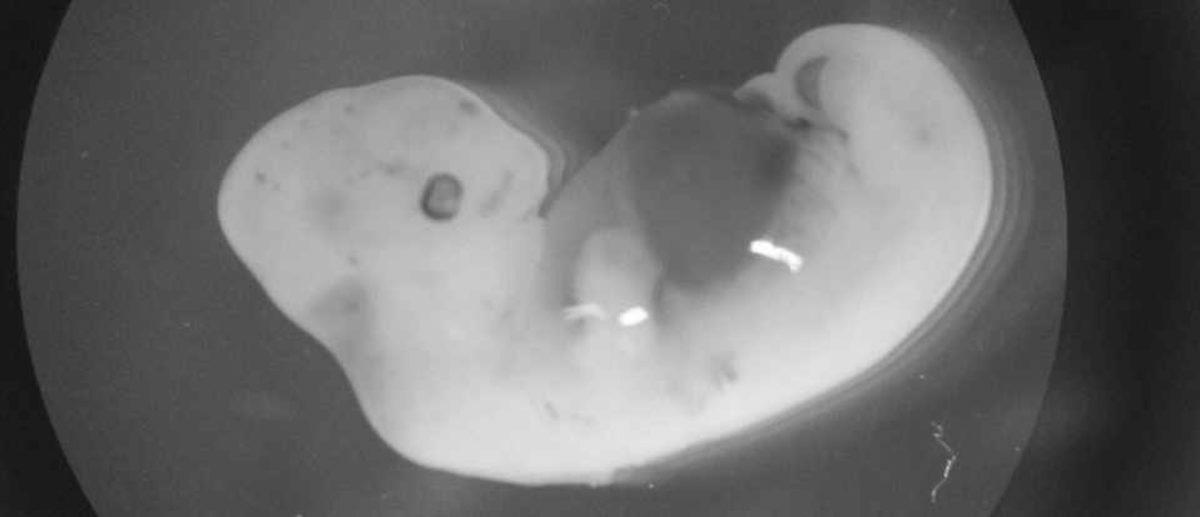

Deneyde aynı zamanda kayda değer miktarda insan kök hücresi kullanılmadı. Koyun embriyosundaki hücrelerin yalnızca %0,01'i insana aitti ve bu hayli düşük bir oran. İnsan organlarının gelişmesi için nerdeyse %1 oranında insan kök hücresi gerekiyor. Koyun/insan embriyosu, tıpkı domuz/insan melezi gibi 28 gün sonra yok edildi.